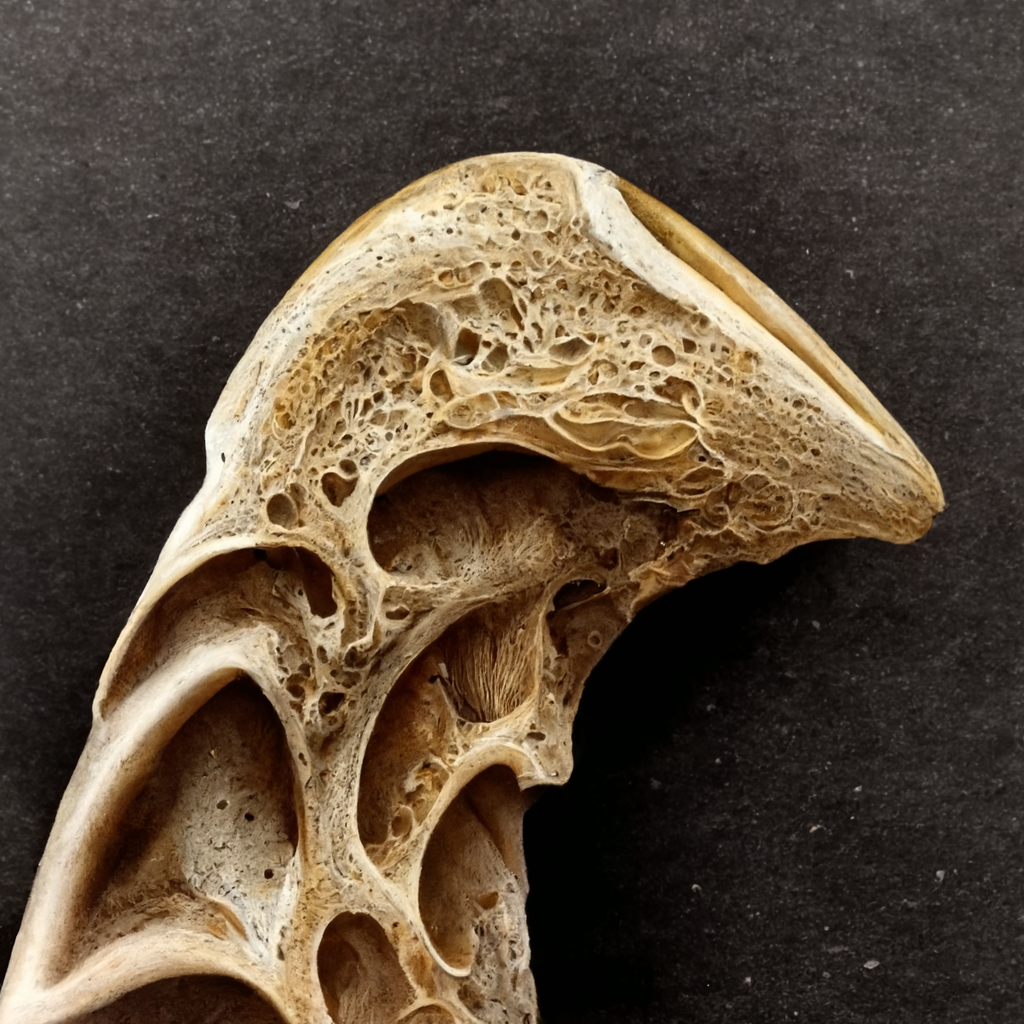

Röntgenler: Diz ekleminin durumunu değerlendirmek için yaygın olarak röntgen görüntüleme kullanılır. Röntgenler eklem aralığında daralma, osteofit (kemik çıkıntısı) oluşumu ve artritin göstergesi olan kemik yapısındaki değişiklikleri gösterebilir.

Manyetik Rezonans Görüntüleme (MRG): MRG taramaları, kıkırdak, bağlar ve tendonlar gibi yumuşak dokular da dahil olmak üzere diz ekleminin daha ayrıntılı görüntülerini sağlayabilir. MR, eklem hasarının boyutunu değerlendirmeye ve diz ağrısına katkıda bulunabilecek diğer durumları tespit etmeye yardımcı olabilir.